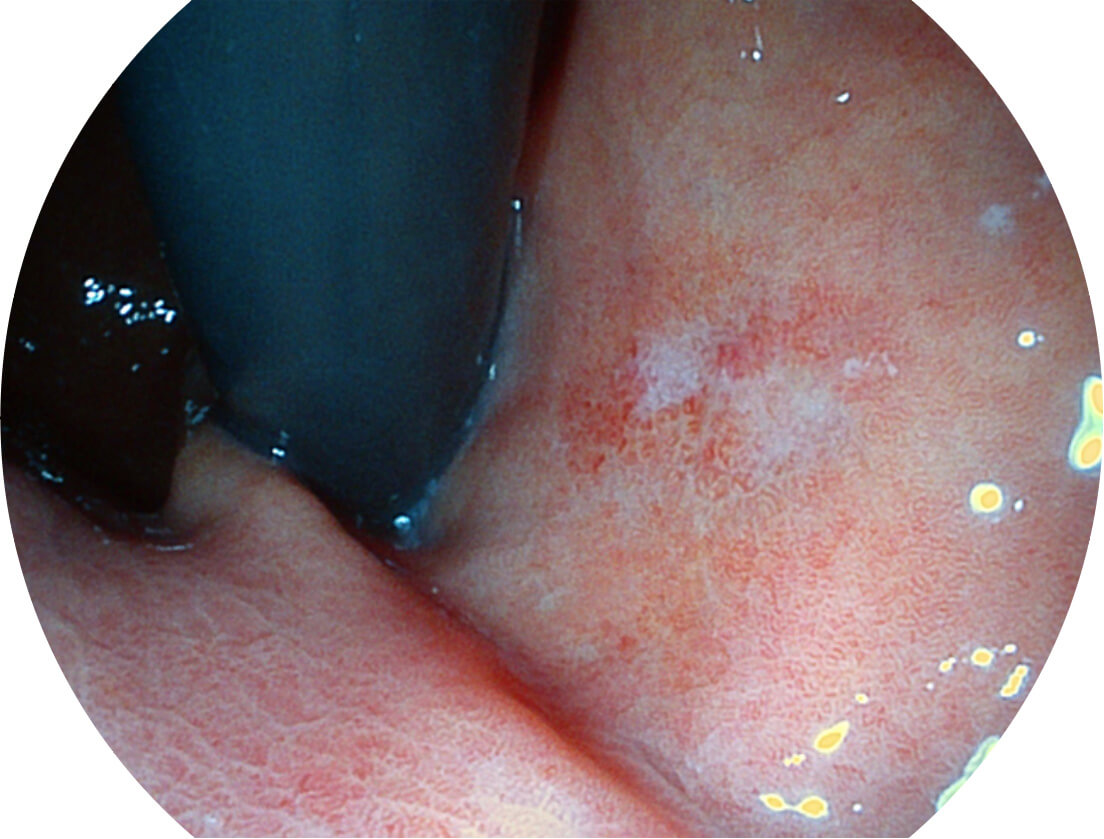

强调浅层黏膜结构的同时,保证照明亮度和提升浅层微血管与中层血管颜色对比度,病变边界更清晰。

白光图像